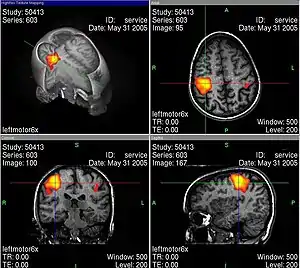

L’usage de l’imagerie cérébrale dans des programmes de recherche en neuropsychologie nécessite de bien maîtriser tous les artefacts et biais statistiques possibles, par exemple lors de l’IRMf en faisant des moyennes spatiales, temporelles et interindividuelles. La base de cet examen est de déterminer des corrélations entre certaines tâches mentales (langage, attention, mémoire…) et des activations spécifiques de zones du cerveau[30].

Les activités électriques du cerveau conduisent à des variations de tension électrique à la surface de la tête, que l'on peut enregistrer avec des appareils convenables. Les neurosciences cognitives actuelles reposent très largement sur le procédé d'imagerie par résonance magnétique fonctionnelle (IRMf). En même temps, ce genre de méthode soulève déjà une série de questions éthiques. Au moyen de l'IRMf, l'activité dans le cerveau peut être mesurée avec une bonne définition spatiale et temporelle. Cette technique conduit à des problèmes éthiques en particulier quand on trouve au moins grossièrement des corrélations entre l'activité neuronale et l'état conscient du sujet. Comment se comporter quand on sait par des méthodes neurologiques, et non par ce qu'elle en dit, qu'une personne pense à quelque chose ou le sent ?

En outre, les technologies correspondantes ne sont pas encore complètement sûres. Judy Illes et ses collègues du Neuroethics Imaging Group de l'université Stanford indiquent la force suggestive des images d'IRMf, qui cachent souvent des problèmes réels d'analyse des données[31].

Les images d'IRMf bien connues (voir par exemple ci-contre) sont toujours interprétées selon des modèles qui en permettent la lisibilité. Pendant une tâche cognitive, le cerveau est constamment actif dans un grand volume, et il faut trier pour obtenir des images significatives, dépourvues de toutes les activités apparemment secondaires. Ce genre de tri se fait avec une méthode de soustraction : par exemple si l'on s'intéresse à une tâche cognitive K, alors on mesure l'activité du cerveau dans une situation S1 dans laquelle K est accomplie. Ensuite, on mesure l’activité dans une situation de contrôle S2 qui ressemble à S1, mais qui n'a a priori rien à voir avec la tâche K. Finalement, on soustrait les activités mesurées dans S2 de celles mesurées dans S1, pour voir les activités corrélées avec la tâche K de façon spécifique. Illes souligne qu'il faut toujours garder en tête ces aspects interprétatifs, ce qui peut facilement passer inaperçu devant un tribunal, parce que les juristes n'ont probablement aucune compétence en neurologie.

Turhan Canli explique : « L'image d'un type d'activité basée sur une étude de mauvaise qualité ne peut pas être visuellement distinguée de celle d'une étude exemplaire. On doit être un habile spécialiste pour éventuellement remarquer la différence. C'est là que réside le grand danger d'abus des données d'imagerie auprès d'un public non éduqué, comme le jury d'une cour d'assises. Si l'on regarde les images, on peut facilement oublier qu'elles représentent des déductions statistiques et jamais une vérité absolue[32] ».

Des études neurologiques récentes ont permis une localisation plus précise des lésions cérébrales de Gage. La barre métallique a en partie détruit le cortex préfrontal, c'est-à-dire la partie du cortex cérébral située au plus près du front. Dans ce cas, ce n'est que la partie ventromédiale du cortex préfrontal qui a été endommagée (voir figure). Les études neuropsychologiques ont montré que Gage n'est pas un cas unique. Tous les patients qui ont une lésion dans le cortex préfrontal ventromédiale présentent cette perte des capacités émotionnelles, malgré une conservation des capacités intellectuelles.